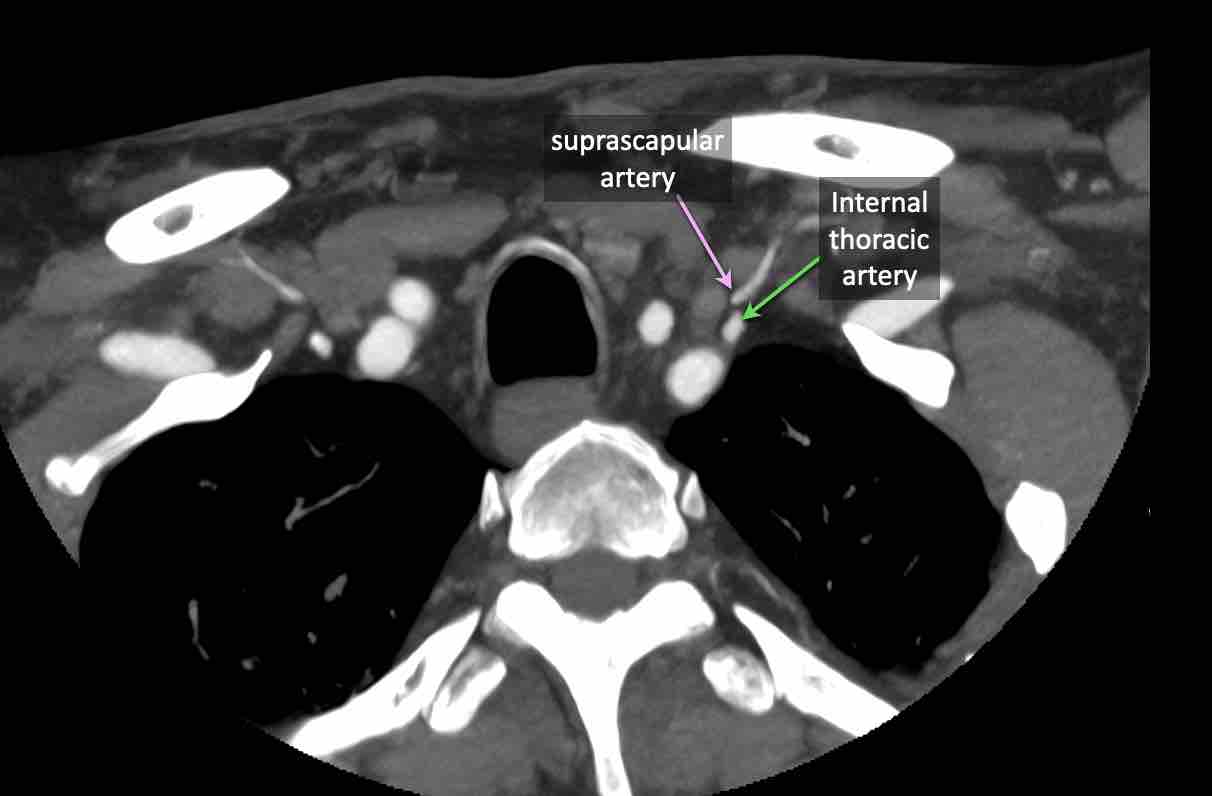

Động mạch cổ ngang

Cuộn qua các hình ảnh để xem giải phẫu của động mạch cổ ngang.